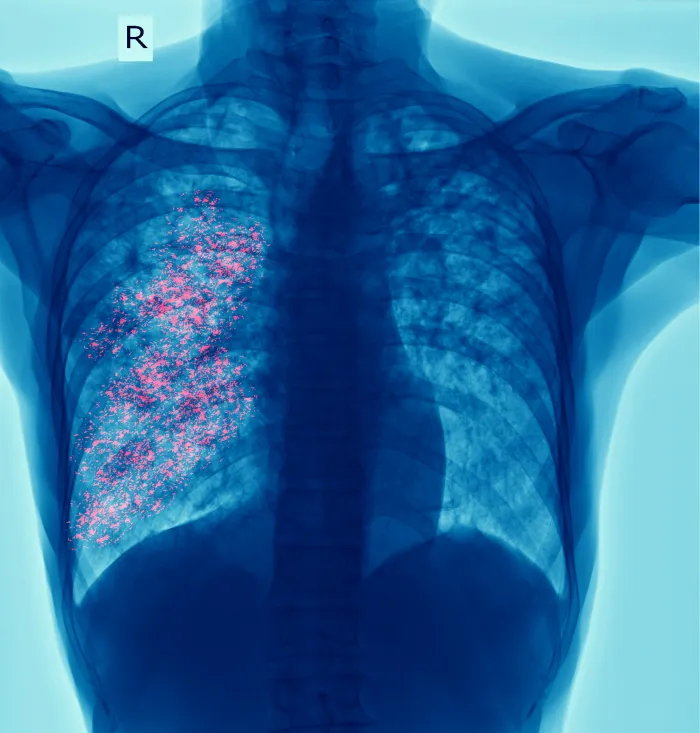

The Role of Artificial Intelligence in Reading Chest X-rays

Chest X-rays are a common TB screening tool, but their interpretation requires a skilled radiologist, a resource often scarce in high-burden areas. Artificial intelligence (AI) algorithms are now being trained to read chest X-rays with remarkable accuracy, flagging suspected TB cases in seconds. This technology can be deployed on mobile phones or tablets, making mass screening in remote communities a reality and ensuring that the latest diagnostic tools for tuberculosis are accessible to all.